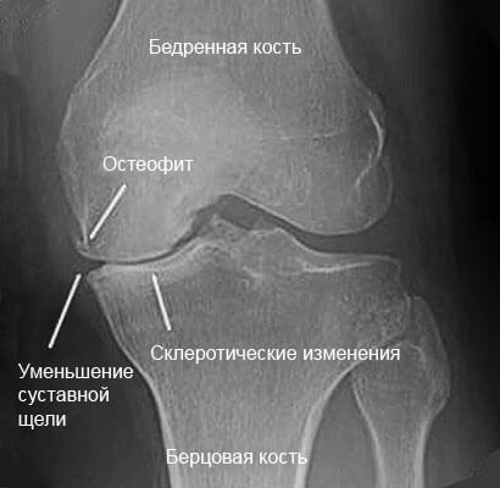

Одним из заболеваний при котором «бушует» ноющая боль — это остеоартроз.

Остеоартроз поражает структуру хрящевой прокладки, находящейся между суставными поверхностями. Трение суставных поверхностей друг о друга заставляет человека испытывать ноющую боль. Болеть коленный сустав начинает вечером и утром, а также появляется отек и покраснение на коже.